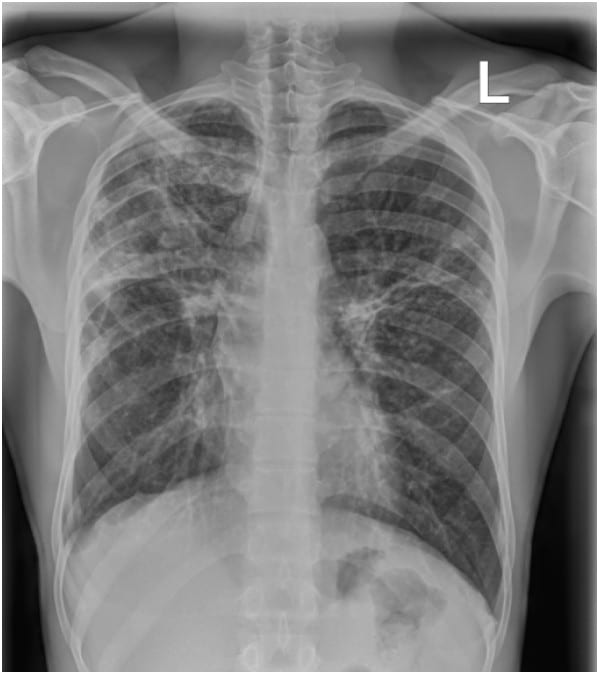

Unlike symptom screening, imaging can reveal structural changes in the lungs, even in patients who do not report symptoms.

“Even those that are asymptomatic, you can begin to see features on the lung image that suggest TB.”

Systems that provide additional image information — such as separating soft tissue and bone structures — are being introduced in some regions to support more detailed interpretation of chest images.

KA Imaging’s Reveal 35C detector, for example, is currently installed in both Nigeria and Kenya as part of local imaging initiatives. These systems aim to provide multiple image outputs from a single acquisition, which may support clinicians in identifying subtle lung abnormalities.

A 22-year-old male presented with a one-month history of dry cough and chest pain. Chest X-ray findings were suggestive of tuberculosis, later confirmed by GeneXpert testing.